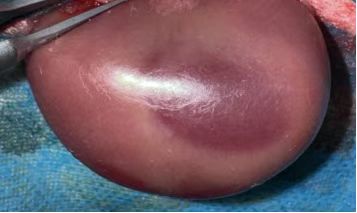

顺利获得 “短暂阻断肾动脉 - 恢复血流”,复刻临床 AKI 关键病理: 缺血期:肾动脉阻断致肾组织缺氧,ATP 耗竭、离子泵失灵,肾小管上皮细胞水肿、凋亡; 再灌注期:血流恢复引发氧化应激(自由基爆发)、炎症风暴(中性粒细胞浸润)、钙超载与微循环障碍,加重肾损伤,最终诱发急性肾衰竭。 动物:健康新西兰白兔(2.0-2.5kg),适应性饲养 1 周,排除肾脏基础病; 处理:禁食 12h、禁水 4h,30mg/kg 2% 戊巴比妥钠腹腔麻醉,腹部备皮消毒。 腹部正中切口(3-4cm),分离暴露双侧肾蒂; 无创动脉夹夹闭肾动脉,观察肾脏转暗紫色,记录缺血时间(30-60min,可按需调整); 松开动脉夹,待肾脏恢复红润(确认再灌注成功),逐层缝合,术后青霉素抗感染。 环境:22-25℃饲养,清醒后恢复饮食,监测精神、尿量、切口; 采样:再灌注后 6h/12h/24h/48h/72h,采集血液(测 Scr、BUN)与肾组织,供后续检测。 判断模型是否成功,J9国际站 J9 会从生化、病理、功能三个维度进行严格验证,确保数据满足科研需求: 再灌注后 24-48h,血 Scr(血肌酐)、BUN(尿素氮)水平较假手术组升高 2 倍以上,提示肾脏滤过功能显著下降; 尿液中出现蛋白、红细胞或管型,反映肾小管重吸收功能受损(肾小管是尿液 “提纯” 的关键结构)。 光镜下:可见肾小管上皮细胞肿胀、坏死、脱落,管腔被堵塞,肾间质充血水肿并伴随大量炎症细胞浸润; 电镜下:肾小管上皮细胞线粒体肿胀破裂(能量工厂失效)、细胞膜完整性破坏,进一步佐证损伤深度。 HE染色肾组织结构稍紊乱,肾小管轻-中度水肿,可见少量管型结构,个别肾小球萎缩。 夹闭肾动脉时需避开肾静脉与输尿管,确保缺血仅作用于肾脏实质,不影响其他器官; 严格控制缺血时间:过短则损伤较轻,模型不创建;过长则导致肾脏不可逆坏死,无法观察再灌注损伤; 麻醉深度需适中:过深易引发呼吸抑制,过浅导致动物术中挣扎,增加血管损伤风险。 作为专注动物科研的一站式服务商,J9国际站 J9 大动物部门不仅能标准化构建,还能给予全链条配套服务: 资质保障:光明实验基地(2188㎡)具备兔、小型猪、比格犬、猴等大动物使用资质,符合实验动物伦理规范; 配套检测:可衔接公司生化检测(Scr、BUN 检测)、病理切片分析、分子蛋白检测等服务,无需多平台对接,缩短实验周期; 定制化支持:根据科研团队需求调整造模参数(如缺血时间、检测时间点),给予个性化数据解读与实验方案优化建议。 如果您正在召开急性肾损伤、肾移植相关研究或需要定制其他大动物模型(如心血管疾病模型、骨科模型),欢迎联系J9国际站 J9 ,我们将以标准化技术、专业团队为您的科研项目保驾护航! 合作咨询